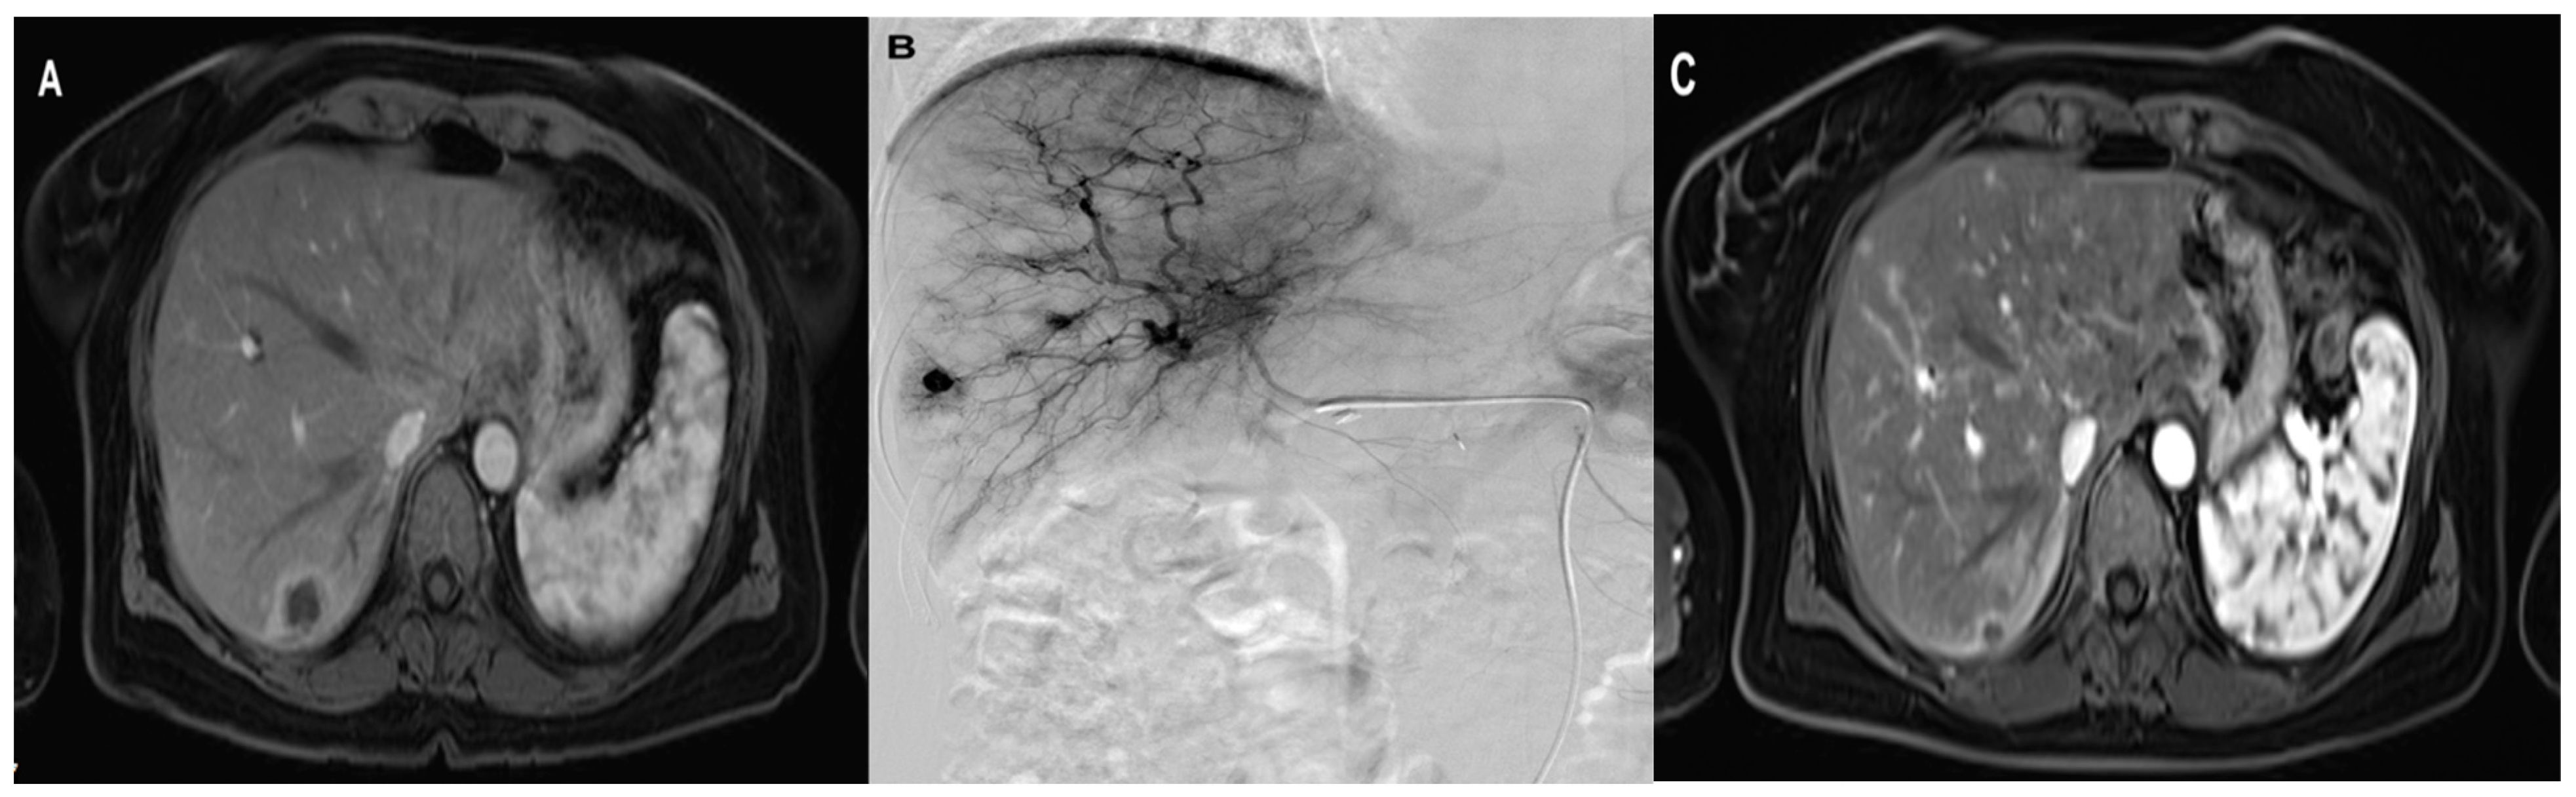

The initial and final mean diameters of the metastatic lesions in Lipiodol + DSM-TACE were 4.5 cm (SD ± 2, range 1.4–7.8 cm) and 3.5 cm (SD ± 2, range 0.9–7.5 cm), respectively (Table 3). The Wilcoxon signed-rank test confirmed a significant metastases diameter difference in Lipiodol + DSM-TACE with an average diameter reduction of 25% (p = 0.002). Figure 3 demonstrates an exemplary treatment course of group Lipiodol + DSM-TACE.

Figure 3.

A 47-year-old woman with solitary liver metastasis in the right liver lobe treated with three sessions of Lipiodol + DSM TACE with Gemcitabine, Cisplatin, and Mitomycin. (A) pre-treatment axial MRI (B) During TACE (C) post-treatment axial contrast-enhanced MRI shows the significant downsizing of the metastasis.

The initial and final mean metastasis diameter for the DSM-TACE group was 4.0 cm (SD ± 1.5, range 1.2–7.1 cm) and 3.1 cm (SD ± 1.2, range 1.9–5.4 cm). The diameter reduction for metastatic lesions after the DSM-TACE therapy was significant, 16.4% on average (p = 0.033).

The initial metastasis diameter was not significantly different between the two groups (p = 0.650). Likewise, the two study groups showed no significant difference in final metastasis diameter (p = 0.614). The slightly higher diameter reduction in group Lipiodol + DSM-TACE compared to DSM-TACE was not statistically significant (p = 0.545).